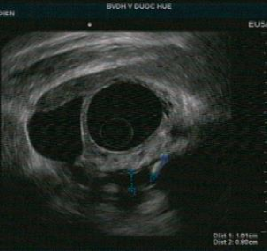

Tổn thương ống tụy: sỏi ống tụy chính, giãn ống tụy, thành của ống tụy chính không đều, tăng âm thành ống tụy chính. Nhu mô tụy thấy các nốt và dải tăng âm. Chẩn đoán chắc chắn viêm tụy mạn với tiêu chí chính A và bốn tiêu chí phụ.

Tổn thương ống tụy: ống tụy chính không giãn nhưng có tăng âm thành ống tụy. Nhu mô tụy: tổn thương dạng tổ ong, các nốt tăng âm không có bóng lưng kèm các tổn thương trống âm. Chẩn đoán nghi ngờ viêm tụy mạn với 1 tiêu chí chính B kèm 3 tiêu chí phụ.